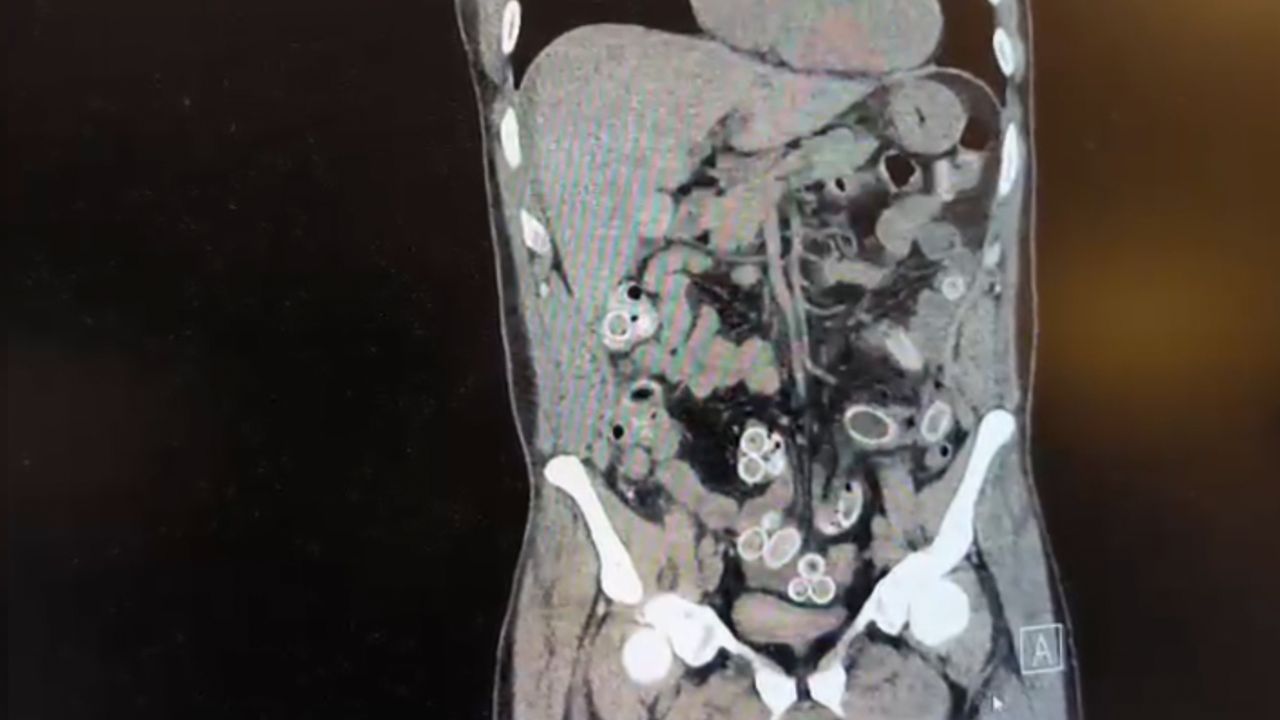

Fas’tan yaklaşık 3 bin kilometre uzaklıktan uçakla Türkiye’ye gelen Cüneyt Ç., 2 gün sonra karın ağrısı şikayetiyle Fulya’daki özel bir hastaneye başvurdu. Yapılan muayenenin ardından Cüneyt G.’nin tomografisi çekildi. Şüphelinin mide ve bağırsaklarında yabancı madde tespit edilmesi üzerine hastane yetkilileri durumu polis ekiplerine bildirdi.

İhbar üzerine çalışma başlatan Beşiktaş Asayiş Büro Amirliği ekipleri, doktorlarla görüşme gerçekleştirdi. Doktorların değerlendirmesi sonrası ameliyata alınan Cüneyt Ç.’nin bağırsaklarından, toplam ağırlığı 259,7 gram olduğu öğrenilen 49 adet esrar macunu çıkarıldı. Şüpheliye ait 1 adet cep telefonu da hastane yetkilileri tarafından polis ekiplerine teslim edildi.